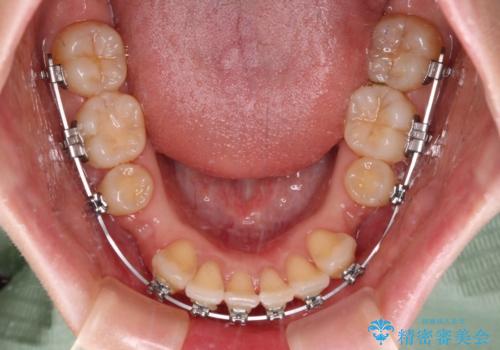

- メタルブラケット

- 2年2ヶ月

上下ともに歯列が前方に突出していたため、上下左右の第一小臼歯4本を抜去し、ワイヤー装置による矯正治療を行うこととしました。

舌の突出癖による影響もあったため、舌のトレーニングを並行して実施しました。

舌の突出癖がなかなか改善されず、上下前歯の接触がやや甘い状態での仕上がりとなりました。

接触が甘い場合、上顎前歯の叢生が後戻りを起こしやすくなるため、治療終了後の保定期間でも舌のトレーニングを継続するように指示しています。